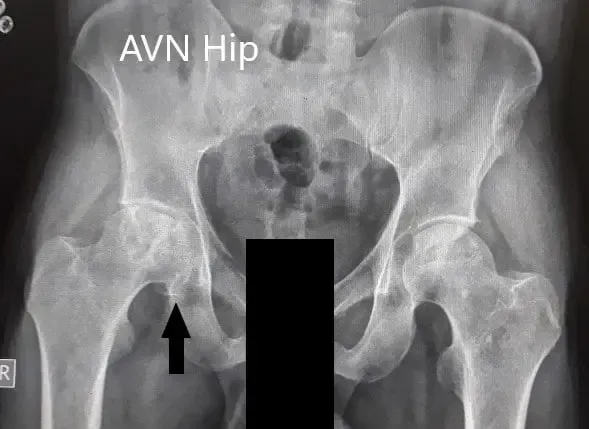

Se obtuvieron imágenes en forma de radiografías que sugirieron el colapso de la cabeza femoral en el lado derecho. Hubo una pérdida de esfericidad de la cadera derecha con esclerosis y quistes subcondrales. La cadera izquierda tenía un contorno intacto. Se recomendó la resonancia de pelvis en ambas caderas.

Radiografía preoperatoria de la pelvis con ambas caderas en vistas anteroposterior y lateral con patas de rana